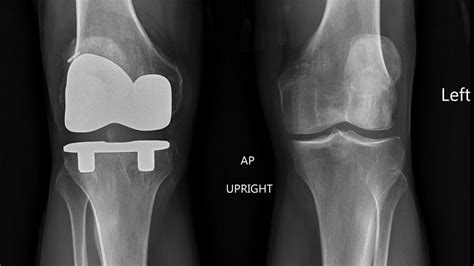

Types of Knee Replacement Surgery

There are several types of knee replacement surgery, including:

- Total Knee Replacement: a procedure where the entire knee joint is replaced with artificial components.

- Partial Knee Replacement: a procedure where only one compartment of the knee joint is replaced.

- Unicompartmental Knee Replacement: a procedure where only one compartment of the knee joint is replaced, usually the medial or lateral compartment.

- Patellofemoral Replacement: a procedure where only the patellofemoral joint is replaced.

- Implantation of artificial components: the surgeon implants the artificial components, which are made of metal and plastic.